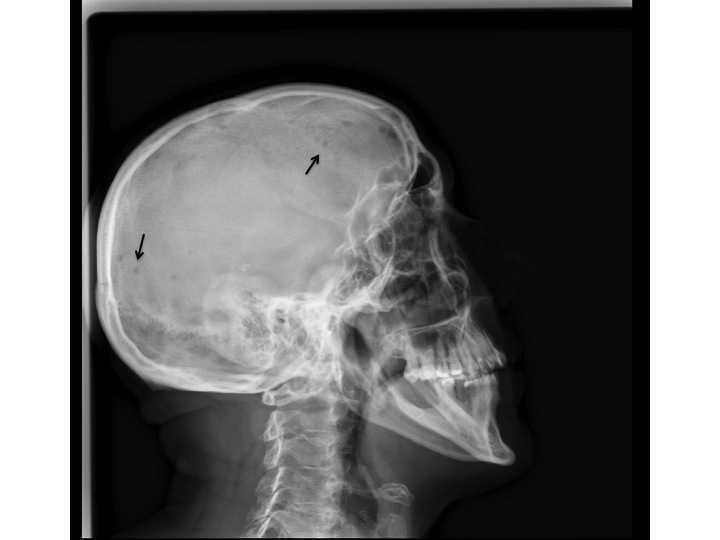

Una serie ósea completa evidenció múltiples lesiones líticas en huesos largos (figura 1) y cráneo (figura 2), sugestivas de mieloma múltiple.

Las lesiones líticas son uno de los criterios diagnósticos y se desarrollan en casi el 80 % de los pacientes. El 58 % de los pacientes refiere dolores óseos en el momento del diagnóstico. La serie ósea todavía es el método recomendado para el diagnóstico de estas, pero solo identifica aquellas con avanzado grado de destrucción ósea, que afectan a un mínimo del 30 % del hueso trabecular, pudiendo llegar a afectar hasta al 50-75 %. La resonancia magnética se recomienda si la serie ósea es normal o si se sospecha un plasmocitoma solitario del hueso3.

Figura 2. Lesiones líticas en el cráneo.